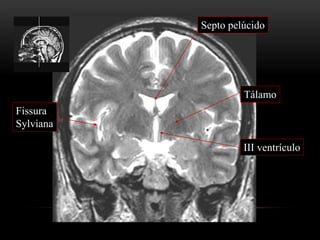

ANATOMIA TOPOGRÁFICA

Plano coronal

Giro frontal

superior

médio

inferior

Foice

inter-hemisférica

Seio sagital superior

Corpo caloso

(joelho)

Ventrículo lateral

(corno frontal)

Lobo

temporal

(corpo)

Quiasma

óptico

Cápsula interna

Núcleo caudado

(cabeça)

Ínsula

a. cerebral

média

III ventrículo

Tálamo

Septo pelúcido

Fissura

Sylviana